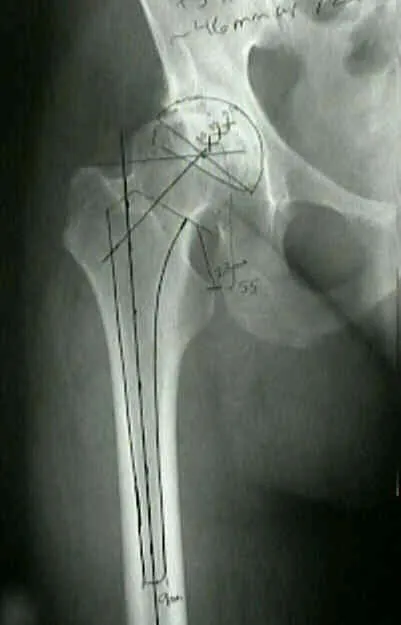

Pre-op Planning & Templating - Blueprint for Bone

Essential for surgical accuracy, aiming to restore native joint anatomy and biomechanics.

- Core Objectives:

- Determine correct implant size, type, and position.

- Precisely plan bone resections.

- Restore limb length equality (LLD), femoral/joint offset, and joint line.

- Anticipate potential intra-operative difficulties (e.g., bone defects, need for augments).

- Methodology:

- Detailed clinical history and physical examination.

- Standardized, calibrated radiographic views (AP/Lateral with magnification marker).

- Templating: Using digital software or acetate overlays.

- Hip: Acetabular inclination (40-45°), anteversion (15-20°). Femoral stem sizing and offset.

⭐ Accurate templating is proven to reduce operative time, blood loss, and improve the accuracy of implant placement, potentially decreasing early revision rates.